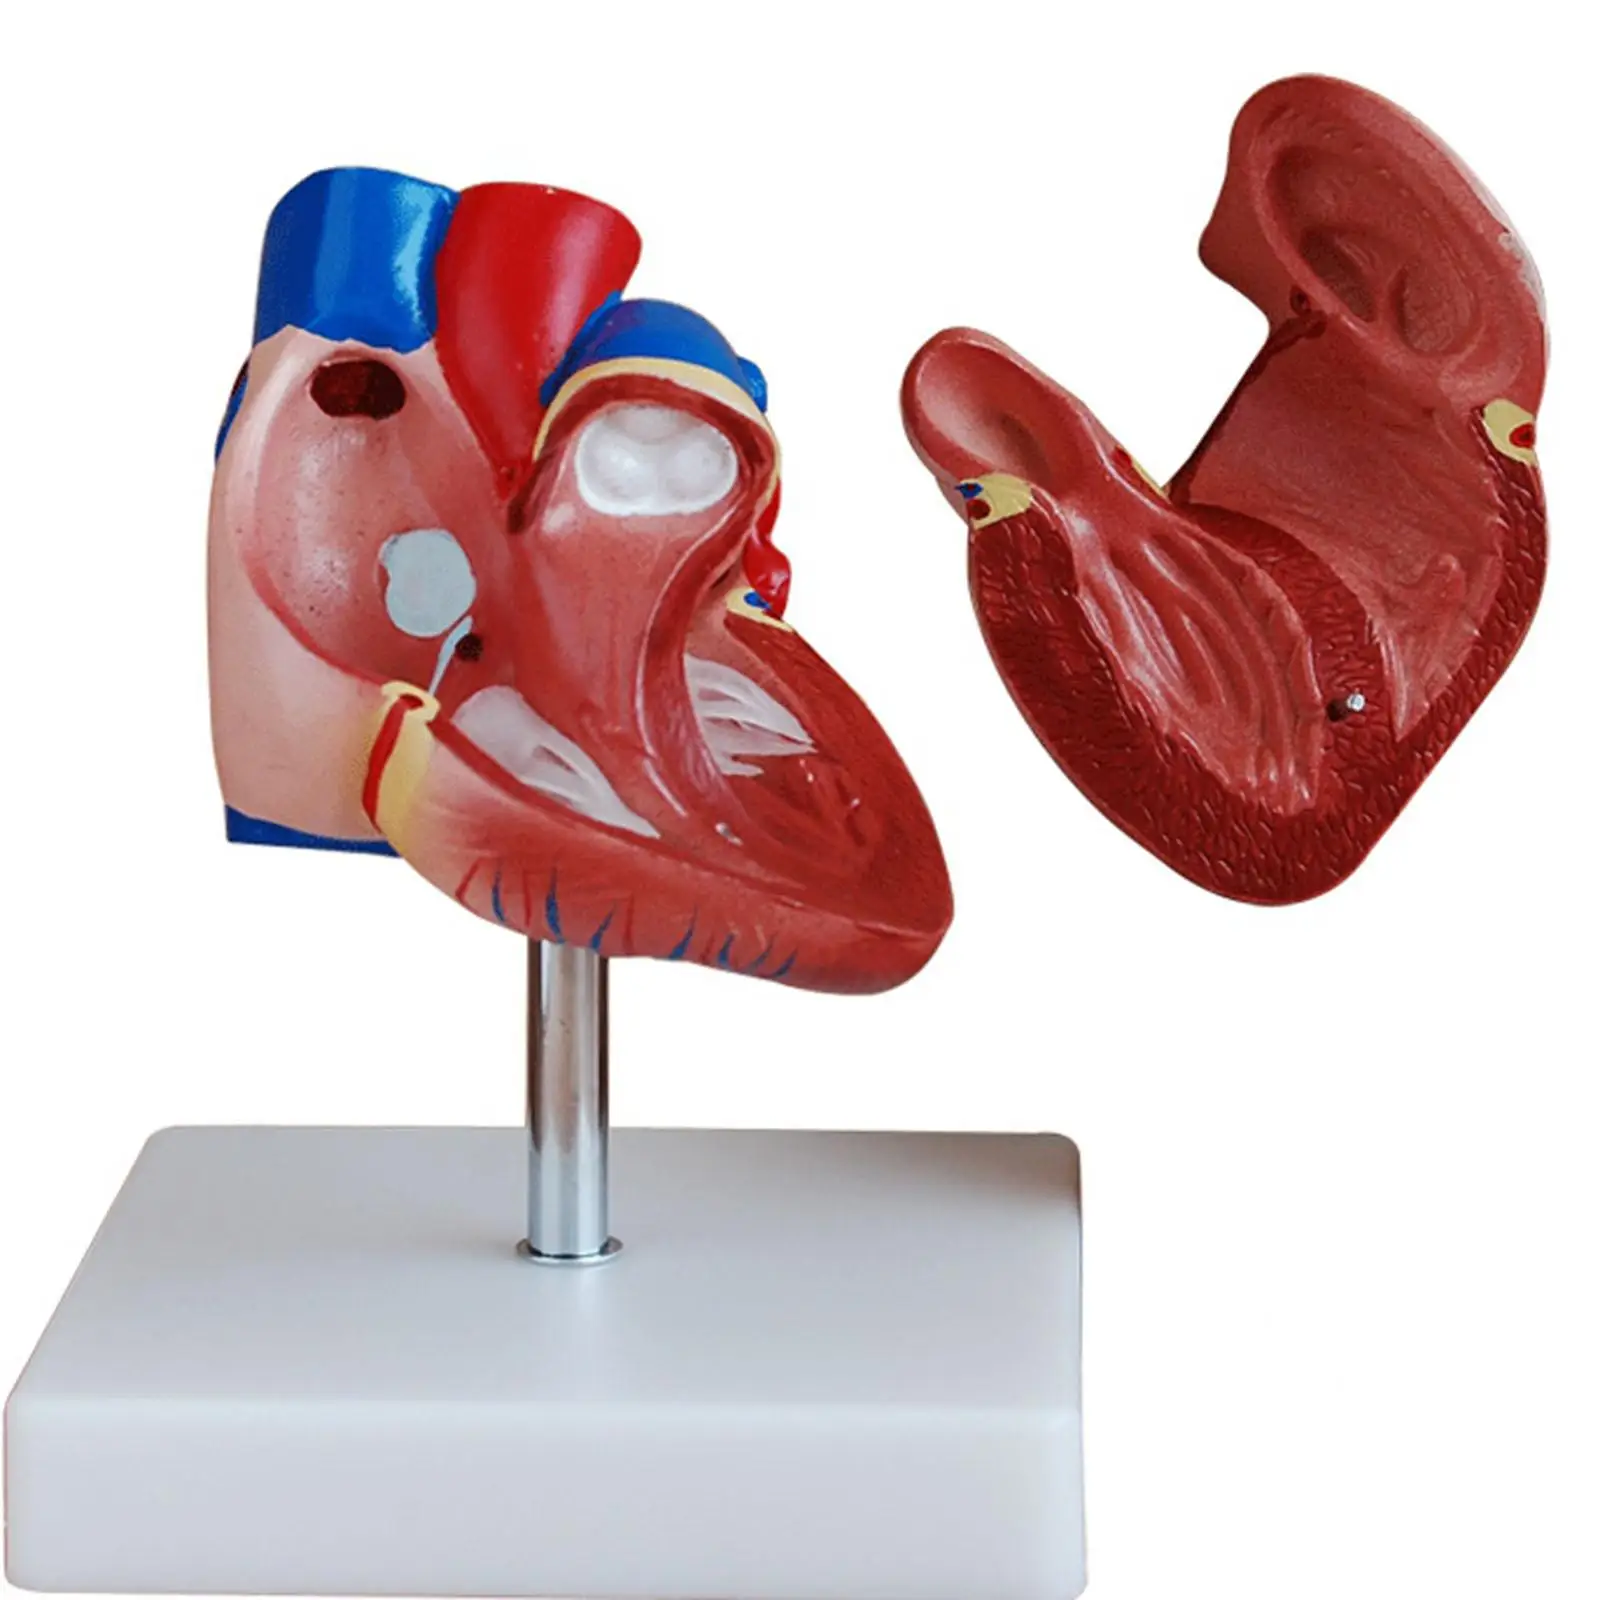

Фотографии и 3D-модели анатомии сердца человека